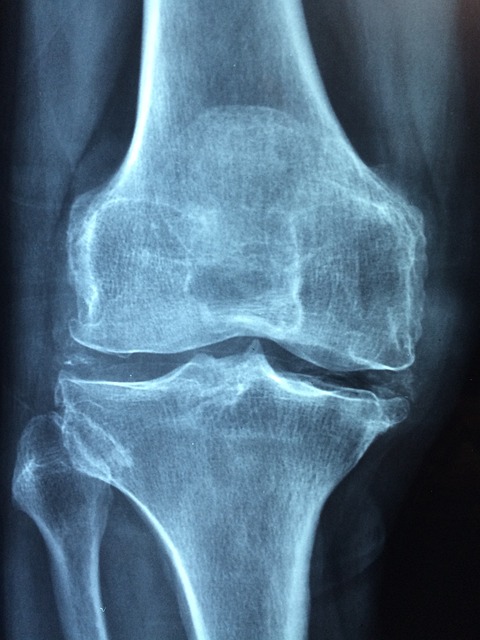

무릎 통증은 연골, 인대, 힘줄 같은 조직에 미세 손상이 생겼다는 신호입니다.

염증이 생기면 무릎에 물이 차고 관절 가동 범위가 제한되며 일상생활조차 불편해집니다.